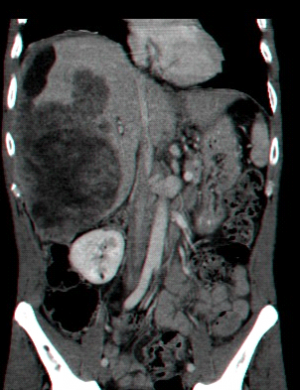

- בדרך כלל אין צורך בביופסיה מחטית של הנגע בתנאי שניתן לראות ב- CT מאפיינים קלאסיים ל- HCC. כיוון שה- HCC היא שאת מאוד וסקולרית הרי שהיא "נצבעת" מהר וחזק בשלב ההזרקה ויש שטיפה מהירה בשלב הפורטלי המאוחר (תצלום 30.10-33.10).

| תצלום 30.10: שאת בכבד הנראית ב- CT. מימין HCC הבולטת על פני הכבד. משמאל פגם מילוי בכבד כביטוי לשאת בכבד (החץ מצביע על השאת). | |

|---|---|

| תצלום 32.10: HCC החודרת לכלי דם ויוצרת קרישים בכלי דם ורידיים. | |